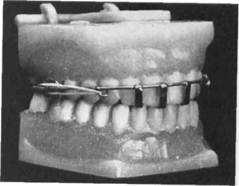

Для расширения верхнего зубного ряда используют также четырехпетельный бюгель, который выпускается промышленностью. Концы бюгеля фиксируют в замковых приспособлениях, расположенных с небной стороны зубного ряда (рис. 13.46). Последние припаяны в горизонтальном направлении к

концам, которые фиксированы на первых молярах. В последние годы вместо замковых приспособлений используют замок Адамика, одна часть которого приклеена к бюге-лю, а вторая — к кольцу.

Для более значительного расширения верхнего зубного ряда фирмы выпускают специальные экспансивные замки, которые позволяют существенно и в короткие сроки расширить зубной ряд (рис. 13.47).